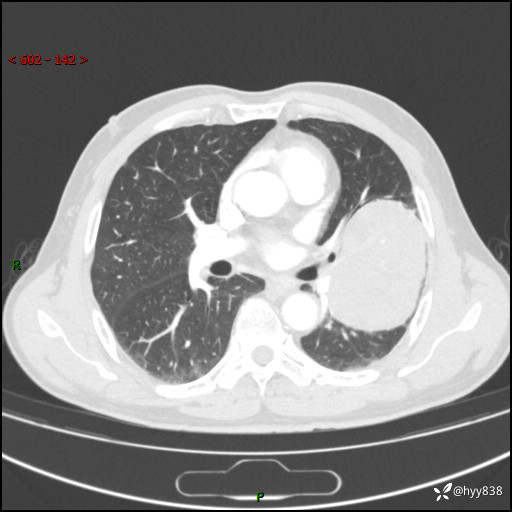

68岁/男,发现左下肺占位5天。如此大的肿块,患者竟然没有症状---结果公布~

【患者信息】:68岁/男

【主诉】:检查发现左下肺占位5天。

【现病史及既往史】:患者于4天前外院行“经尿道钬激光碎石术”,住院期间胸部CT检查发现左下肺肿块,患者平素无明显咳嗽咳痰,无心慌、胸闷、胸痛、呼吸困难、低热、盗汗,无头痛、头晕,无腹痛、腹胀等不适,现患者为求进一步治疗,遂来我院就诊,以“左下肺肿块”收入我科。 患者自起病以来,精神可,睡眠可,饮食可,大小便正常,体重无明显改变。

【检查】:胸部CT增强扫描